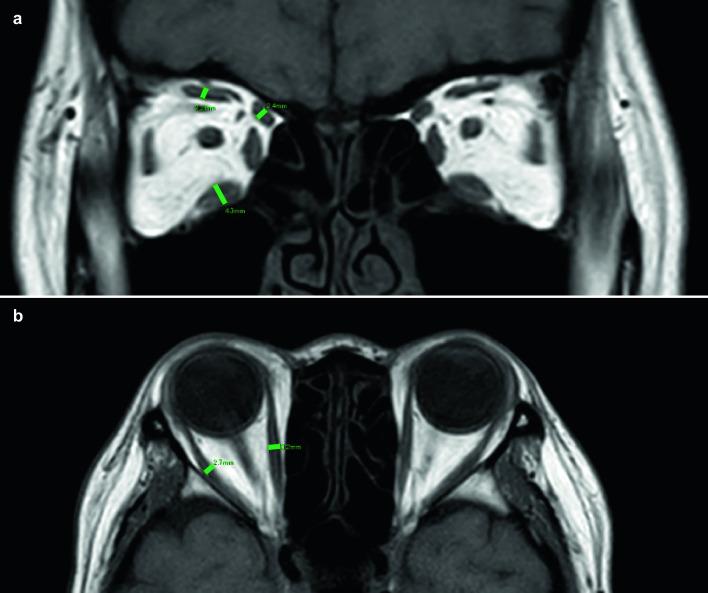

The thyroid-stimulating hormone (TSH) receptor antibody (TRAb), thyroid-stimulating antibody (TSAb), antithyroid peroxidase antibody (ATPO), and antithyroglobulin antibody (ATG) levels in patients diagnosed with TED who underwent orbital magnetic resonance imaging were assessed. The control group comprised the contralateral eye of patients who underwent orbital magnetic resonance imaging (MRI) for unilateral eyelid tumors or orbital disease. The thickness of the bilateral rectus muscles and superior oblique muscles was measured on orbital MRI. Muscle enlargement was classified as unilateral/bilateral and symmetric/asymmetric. The effects of age, sex, smoking history, TSH, thyroid hormone, and thyroid autoantibodies on the muscle thickness and number of enlarged muscles were assessed by use of simple and multiple regression analyses.

The TED and control groups comprised 41 and 44 cases, respectively. The positivity rate of TSAb in patients with TED was 92.7% higher than that of the other autoantibodies. Muscle enlargement was observed in 29 of the 41 cases (70.7%). Older age and higher TSAb levels were identified as significant factors affecting the total muscle thickness and number of enlarged muscles. Bilateral muscle enlargement and asymmetrical muscle enlargement were observed in 17 (58.6%) and 23 (79.3%) of the 29 cases, respectively. The TSAb levels and age had no significant effect on the type of muscle enlargement.